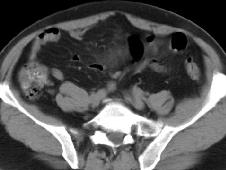

3.CT检查

不但能从其发生的部位鉴器官的肿腹膜后肿,而且还能检查出体积比较小的肠系膜